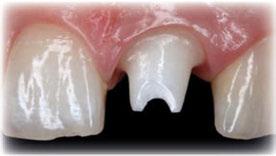

Figuras 4 y 5. Imagen intraoral y de sonrisa de la paciente en la primera visita. En ellas observamos el colapso de la mordida a nivel anterior, con una sobremordida del 100%.

Figuras 6 y 7. Al retirar las prótesis removibles observamos en el arco inferior una gran reabsorción ósea del sector posterior, con elevación del suelo de la boca y la invasión de los tejidos blandos, lo que nos hace suponer que existe una gran atrofia ósea asociada.

Figura 8. En la radiografía inicial ya se hace evidente que los sectores posteriores mandibulares tienen una escasa altura ósea residual y podemos ver desajustes en la prótesis sobre implantes superior del primer cuadrante.